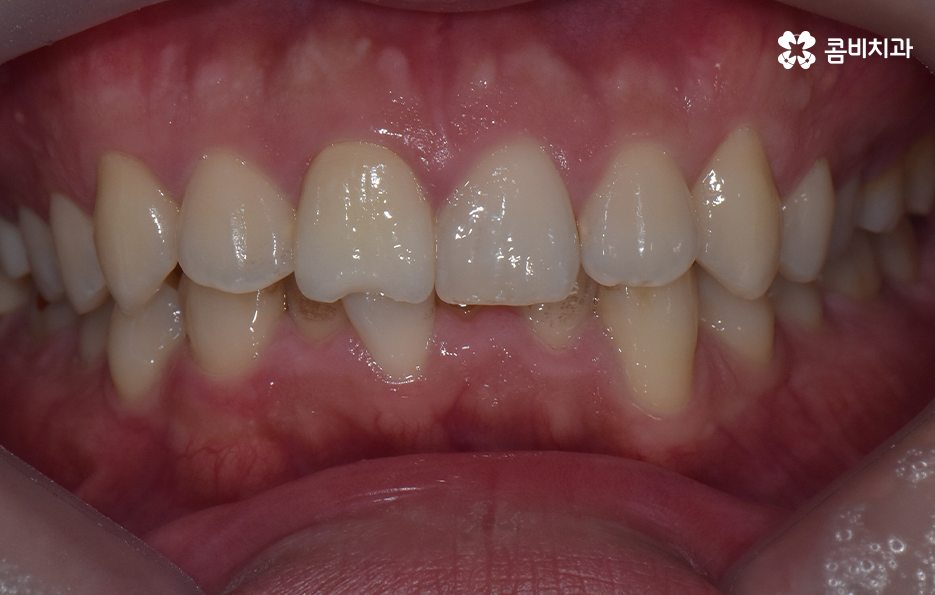

하지만 위에 보시는 환자분의 사례는 윗니와 아랫니의 교합을 고려하고 얼굴형, 골격 등을 고려했을 때도 아랫니만 교정이 가능했던 사례인데 일반적으로 윗니가 아랫니를 살짝 덮고 있어야 하는데 아랫니의 앞니 부분이 유독 안으로 들어와 있었기 때문에 아랫니교정 만으로도 치아교정이 가능했던 사례라고 보시면 좋을 거예요

위 환자분의 사례로 보면 아랫니 중에 하나가 유독 앞으로 튀어나와 있고 나머지 치아는 안으로 들어가 있기 때문에 교합으로 따져볼 때는 아랫니를 전체적으로 앞으로 이동시켜야 했기 때문에 비발치로도 충분히 교정이 가능했고 아랫니교정 만으로도 치료가 가능했어요